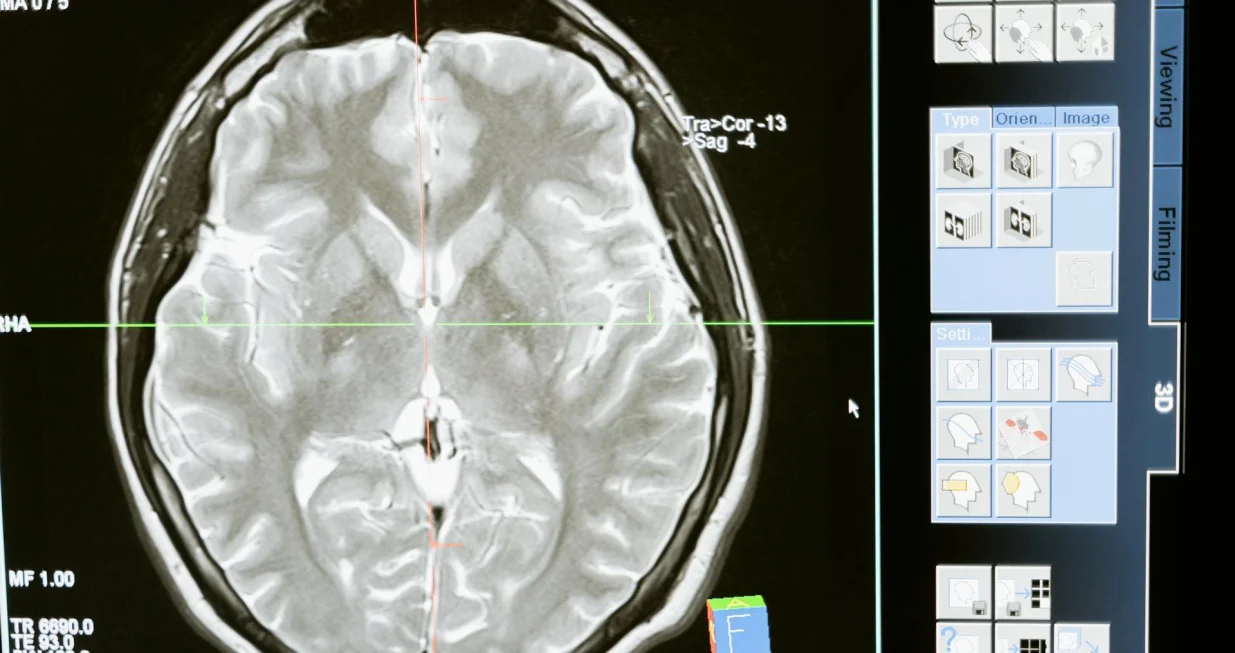

Novi nalazi predstavljeni na godišnjem Samitu američke fiziološke asocijacije (APS) sugeriraju da popularni niskokalorični zaslađivač eritritol može štetno djelovati na krvne sudove mozga, povećavajući oksidativni stres i smanjujući proizvodnju dušikovog oksida – spoja ključnog za širenje krvnih sudova i zdrav protok krvi.

U studiji su istraživači tretirali ljudske moždane mikrovaskularne endotelne ćelije dozom eritritola koja odgovara količini sadržanoj u jednoj porciji zaslađenog napitka. Rezultati su pokazali povišen oksidativni stres i značajno smanjenu proizvodnju dušikovog oksida, što može narušiti sposobnost krvnih sudova da se šire, otežati protok krvi i povećati rizik od srčanog i moždanog udara.